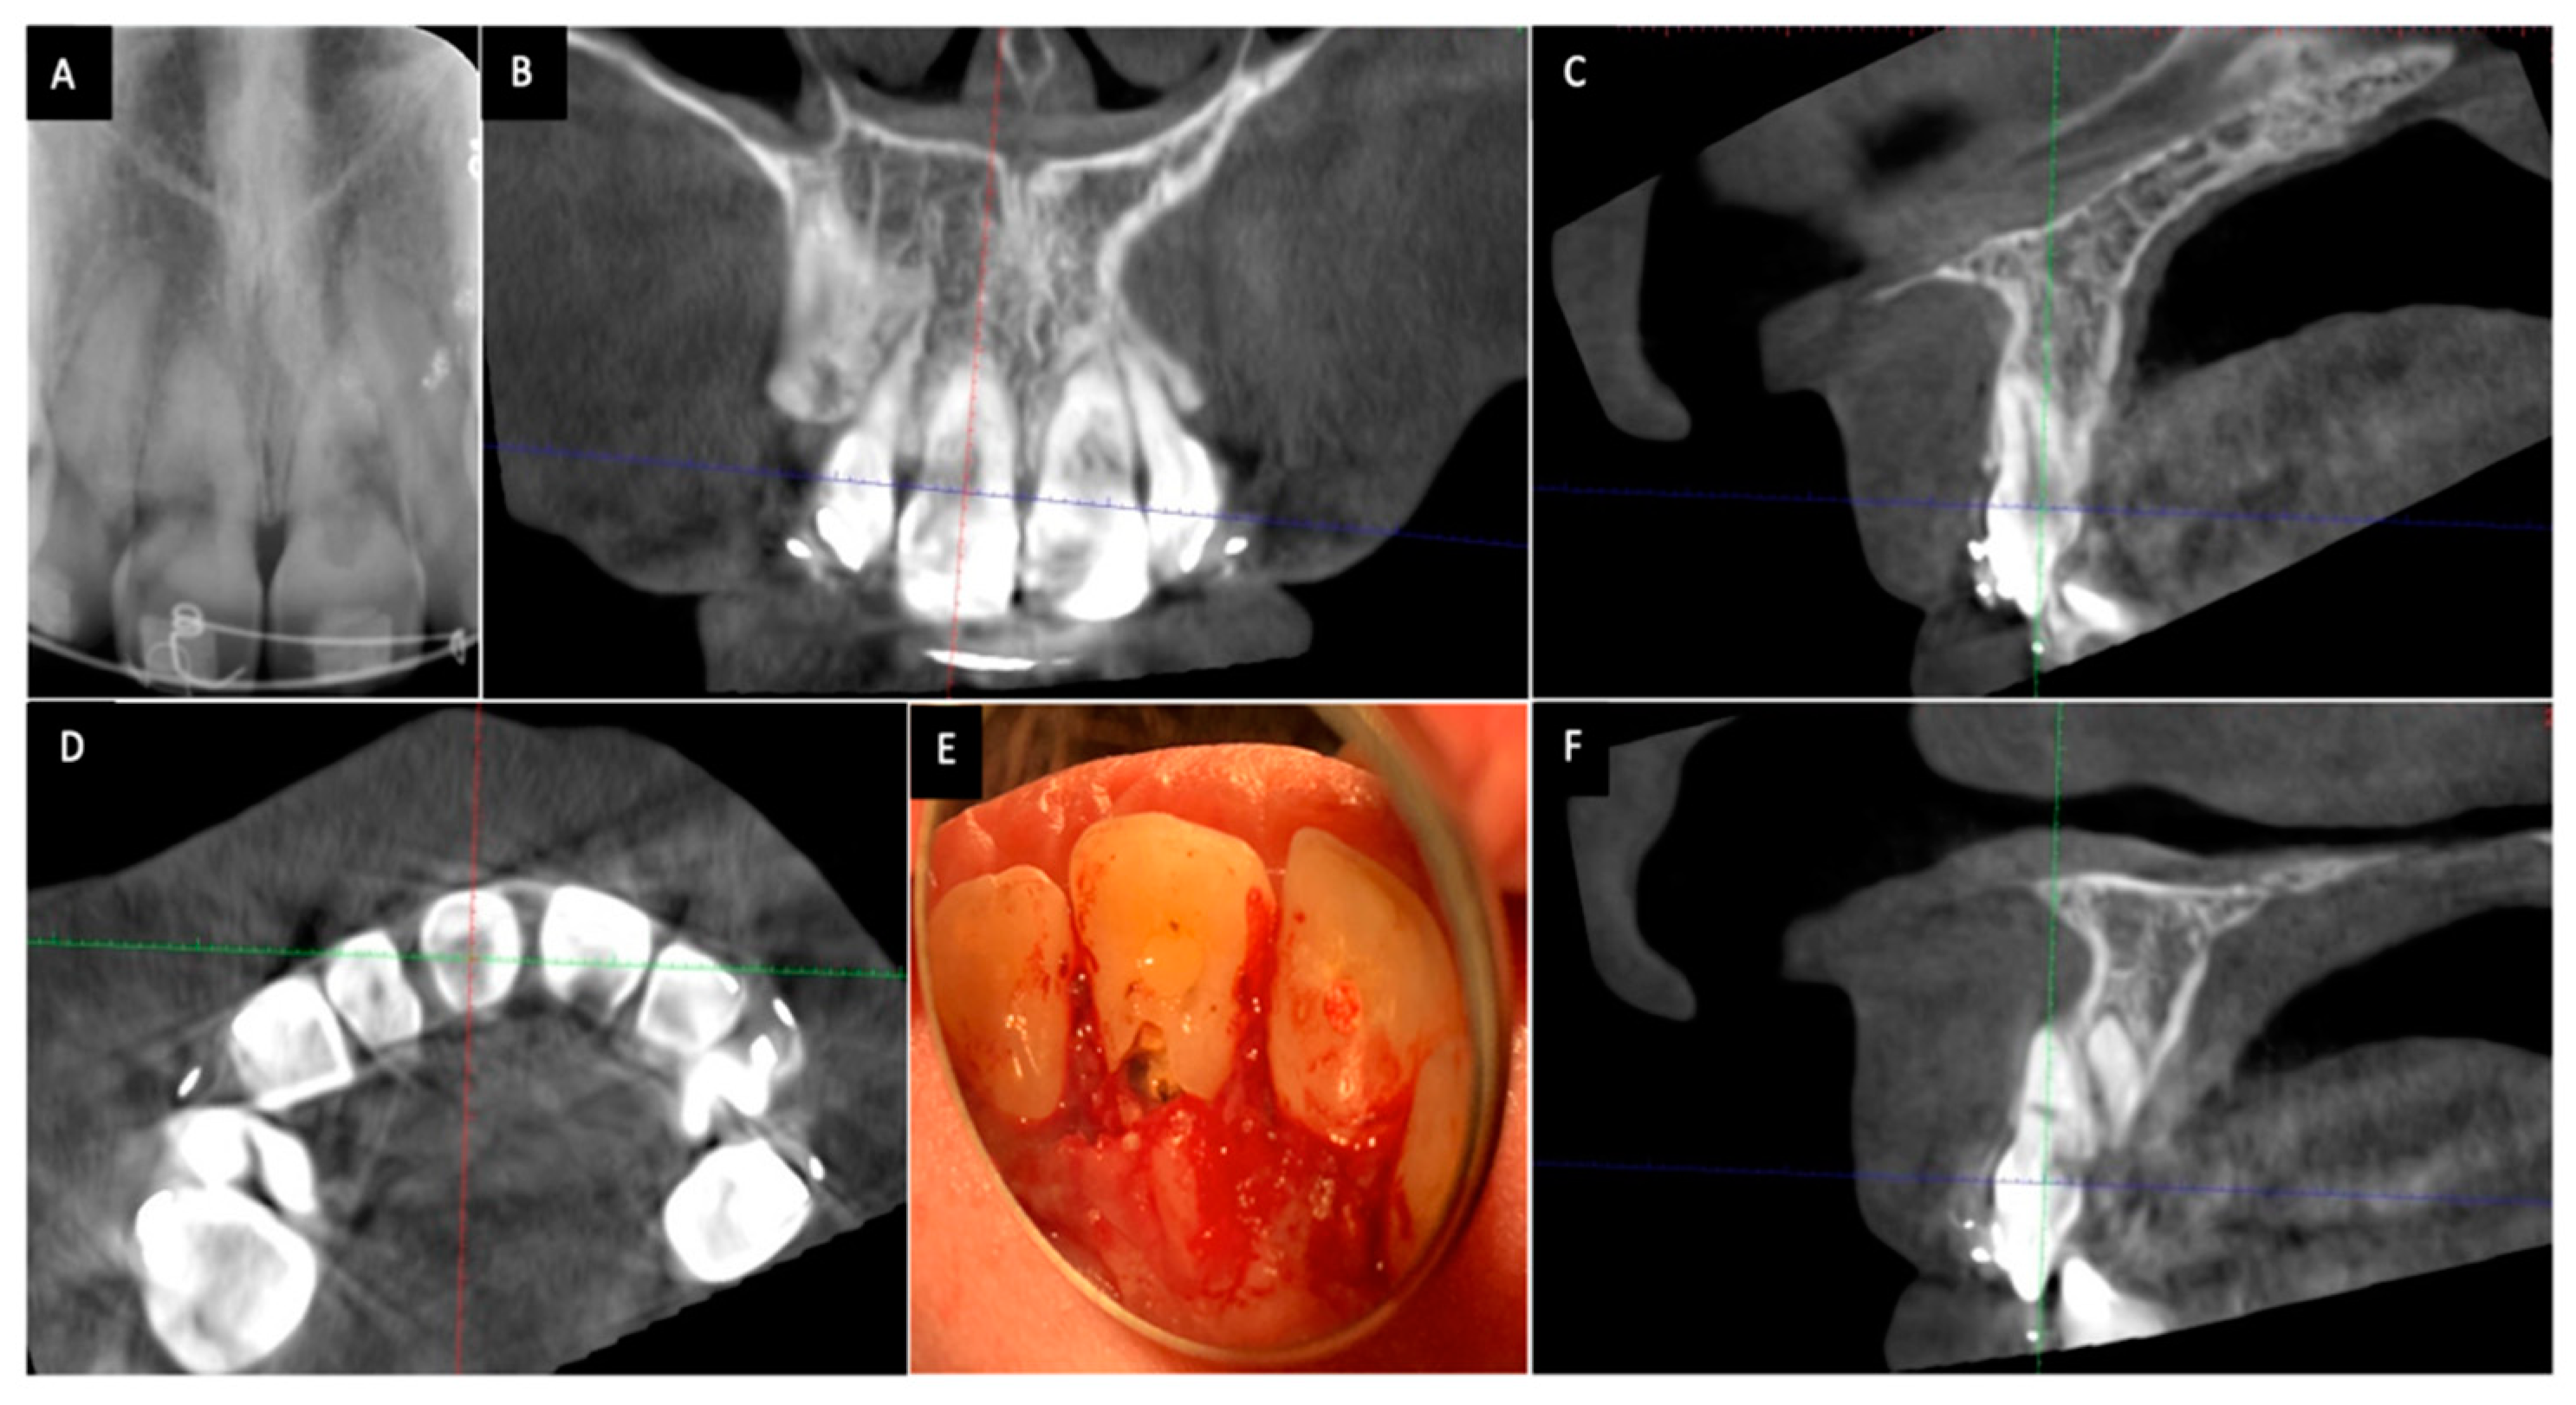

1. فحص السن والتأكد من حالته السنية

قبل البدء بأي إجراء يقوم الطبيب بتقييم شامل للسن. يتضمن ذلك فحصا سريريا وأخذ صور أشعة للتأكد من أن علاج العصب السابق قد تم بشكل جيد وأن الحشوة محكمة الإغلاق عند قمة الجذر ولا يوجد أي التهاب أو خراج حول الجذر. هذه الخطوة حيوية لضمان سلامة الإجراء .

2. فتح بسيط لتجويف السن

تحت عزل تام باستخدام الحاجز المطاطي (Rubber Dam) يقوم الطبيب بإزالة جزء من الحشوة الخلفية للسن للوصول إلى حجرة العصب التي تم تنظيفها سابقا. هذا الفتح يكون محافظا وصغيرا جدا.

3. تنظيف داخلي وتجهيز السن لاستقبال المادة

يتم تنظيف حجرة العصب بعناية لإزالة أي بقايا من مواد الحشو القديمة أو الأنسجة المتحللة التي قد تكون سببا في التصبغ. بعد ذلك يتم وضع طبقة واقية عازلة (Coronal Seal) فوق حشوة قناة الجذر مباشرة مثل مادة الأسمنت الأيونومري الزجاجي. هذا الحاجز ضروري جدا لمنع تسرب مادة التبييض إلى قناة الجذر والأنسجة المحيطة وهو أهم إجراء للوقاية من المضاعفات مثل الامتصاص الجذري.